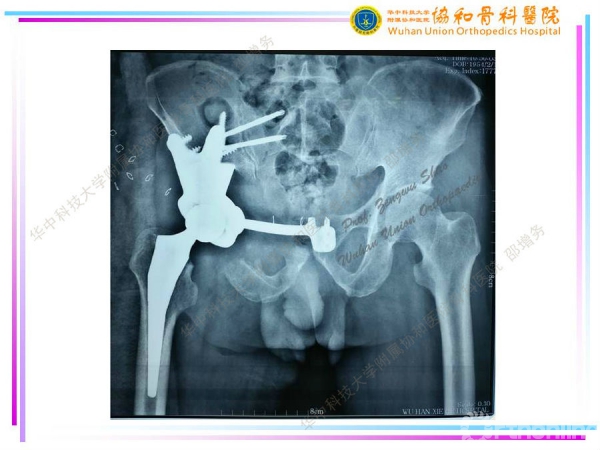

3D打印个性化半骨盆假体在骨盆肿瘤治疗中的应用

编者按--由于骨盆特殊的空间形态及周围复杂的解剖结构,骨盆肿瘤(尤其是髋臼周围肿瘤及骶髂部位肿瘤)的切除与重建一直是骨科医生面临的重大挑战之一。计算机技术、3D打印技术(3D打印骨盆三维模型、3D打印截骨导板、3D打印肿瘤假体)在骨盆肿瘤的应用,可大大提高截骨的准确性及假体的匹配度、缩短手术时间,降低假体相关并发症。2014年11月至2017年3月,华中科技大学附属协和医院骨科医院邵增务教授团队已顺利完成3D打印个性化板骨盆假体治疗骨盆肿瘤15例,近期效果满意,中远期效果有待进一步观察。